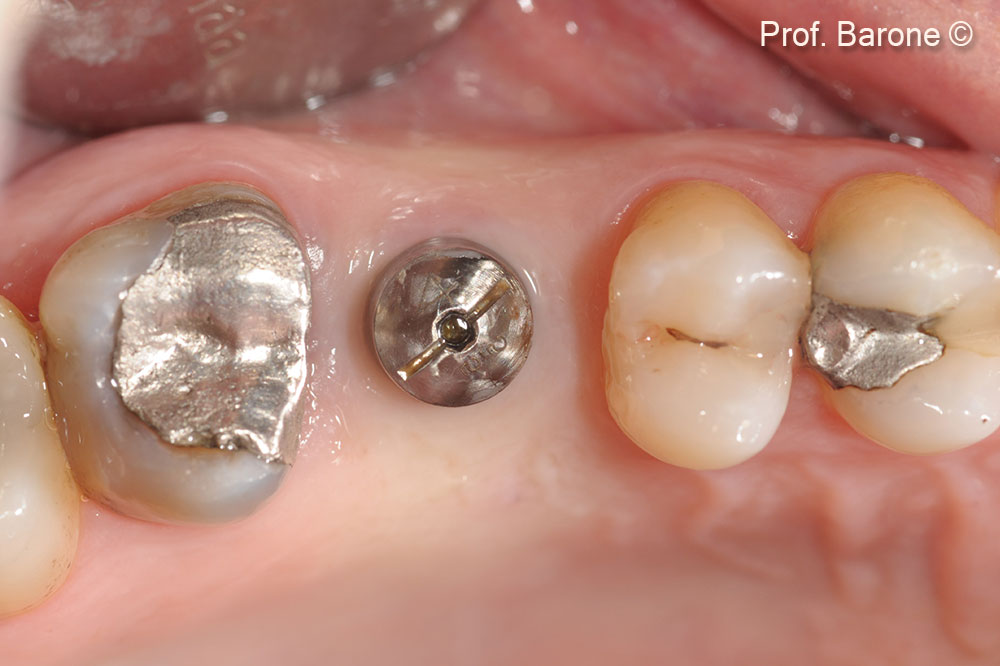

Healing Abutment, Occlusal View